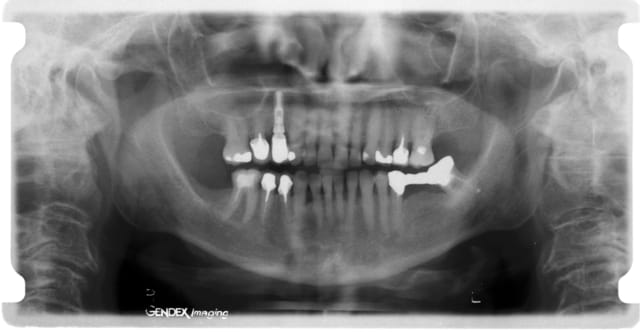

Je joins quand même vite fait avant de partir la pano.

Pano k6vtgj - Eugenol

Deux petites choses sur la pano

1. les 7 sont qd mm toutes absentes ce qui fait qd mm que la pression se pose un peu plus en mésial

2. le bridge du côté gauche peut créer une contrainte mais à droite car courbe de Spee pas top

Question : ton patient a t il un deep-bite au niveau antérieur ou pas ???

Pp